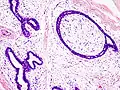

![]() خزعة من نسيج ورم غدي ليفي تحت المجهر (النسيج مصبوغ بصبغة الهيماتوكسين والأيوسين). خزعة من نسيج ورم غدي ليفي تحت المجهر (النسيج مصبوغ بصبغة الهيماتوكسين والأيوسين). | |

نسيج ورم غدي ليفي تحت المجهر (مصبوغ بالهيماتوكسين والأيوسين)